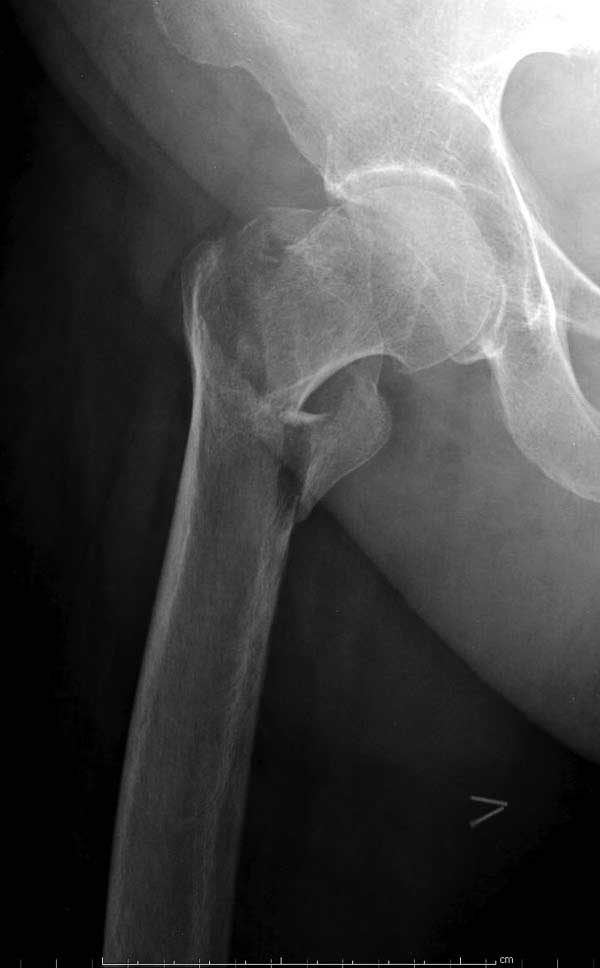

Первые снимки показывают технические погрешности установки DHS. Не была достигнута репозиция, конечность в флексии и шейка в ротации. Сегодня все меньше обращают внимание на параметры для оценки репозиции (S контуры Lowell в обеих проекциях и Garden Alignment Index, в норме 155 и 180 градусов), хотя такие простые тесты помогли бы дорепонировать смещение. Винт находится сзади в головке, что при нагрузке поменяет вектор и вместо компрессии в линии перелома срежет головку-Cut Out!

В зависимости от дистанции линии перелома и латерального кортекса надо использовать разной длины barrel, т.е. конец баррели не должен доходить до пределов перелома. Здесь конец длинного ствола упирается в медиальный фрагмент, что мешает созданию компрессии, а более короткий barrel создал бы запас для компрессии. В боковой пластине вместо 4х можно было ограничится двумя шурупами, потому что головка шурупа в 4.5 мм выдерживает давление до 350 кг.